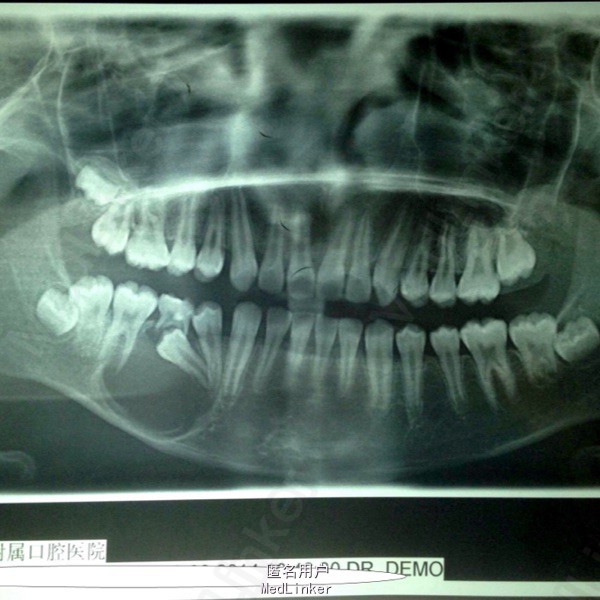

偶然发现右下颌骨包块2月 患者男,11岁,2月前发现右下颌骨区包块,于当地医院就诊,未明确诊断,建议上级医院就诊,遂入我院。

颌面部不对称,口内见右侧下颌颊侧膨隆,大小约3cm*4cm,质硬,不活动,无压痛。黏膜正常。85龋坏,滞留。44-46根尖低密度影,周围高密度致密影,45埋伏阻生。

右下颌骨含牙囊肿 局部开窗引流术,拔除滞留乳牙及埋伏阻生牙。同期取少量标本病检。

术后病检提示含牙囊肿。随访提示局部病变区囊肿缩小,新骨形成。目前仍处于随访阶段,并拟安排后续正畸治疗。 讨论:颌骨囊肿治疗方式非常多,传统填塞碘仿纱条,植骨(粉),引流~考虑患者年龄,后续治疗不适合做种植手术,植骨对正畸治疗有一定影响。综合考虑选择引流法,也取得了预期效果。但囊肿有向成釉细胞瘤转化可能,需术前告知患方,并坚持随访。